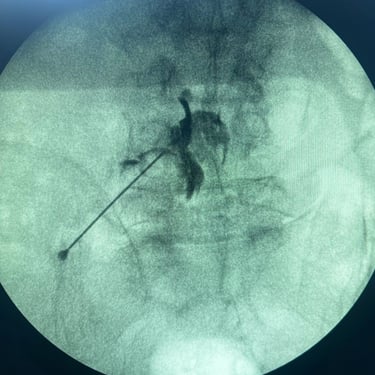

La lumbalgia crónica es una causa frecuente de dolor e incapacidad en el adulto mayor, generalmente asociada a degeneración discal, artrosis facetaria o compresión nerviosa. Cuando el dolor persiste pese al tratamiento convencional, se recurre al bloqueo lumbar selectivo, un procedimiento mínimamente invasivo que consiste en inyectar anestésico y antiinflamatorio alrededor de la raíz nerviosa afectada. Este tratamiento permite identificar el origen del dolor y aliviarlo de manera rápida y efectiva, mejorando la movilidad y calidad de vida del paciente. Es una alternativa segura, ambulatoria y con excelentes resultados en el manejo del dolor lumbar crónico.